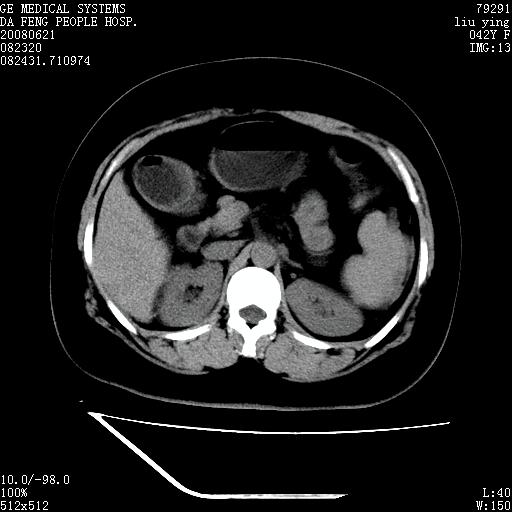

标题: CT14225:女性46岁。当地B超示肝内占位,来我院作CT检查。请 [打印本页]

标题: CT14225:女性46岁。当地B超示肝内占位,来我院作CT检查。请

速升速降,支持肝癌.脾体积增大,形态欠规整,请询问病史是否做过脾动脉栓塞.

速升速降,支持肝癌可能。

快进快出,符合肝癌表现-----------

肝内结节强化特点符合原发性肝癌表现,脾脏改变考虑为增大及先天发育所致。

动脉期病原灶明显强化高于肝密度且中央有无强化区,静脉期强化程度下降明显,延迟低于肝密度,考虑肝腺瘤可能性大,

肝内结节强化特点:快进快出符合原发性肝癌表现

此患者虽然符合快进的特点,却不符合快出的特点,因为门脉期几乎是等密度,不符合肝癌的增强表现,所以我考虑肝局灶性结节增生可能性大